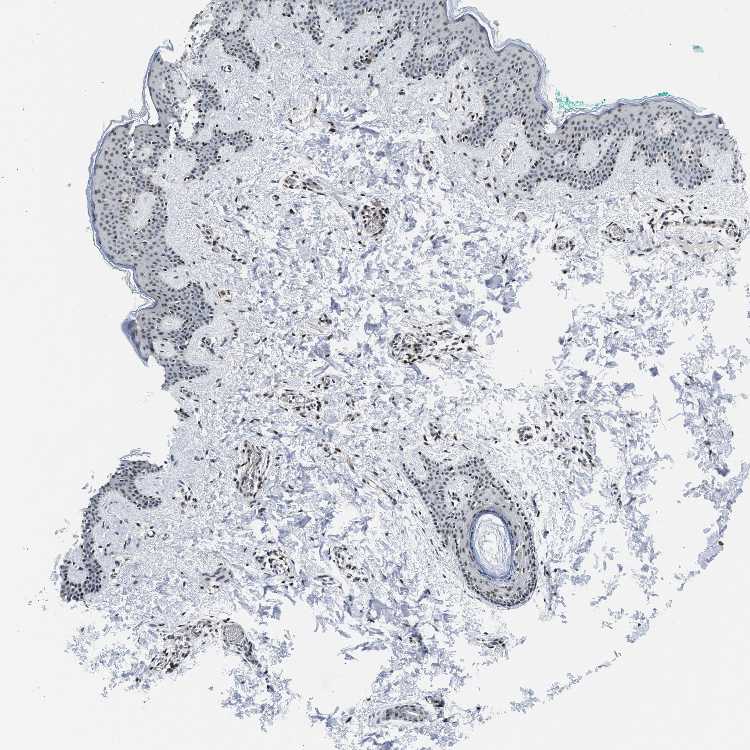

SKIN 1 - Antibody stainingi

Antibody staining in the annotated cell types in the current human tissue is reported as not detected, low, medium, or high, based on conventional immunohistochemistry profiling in selected tissues. This score is based on the combination of the staining intensity and fraction of stained cells.

Each image is clickable and will lead to virtual microscopy that enables deeper exploration of all samples and also displays staining intensity scores, fraction scores and subcellular localization as well as patient and tissue information for each sample.

SKIN 2 - Antibody stainingi